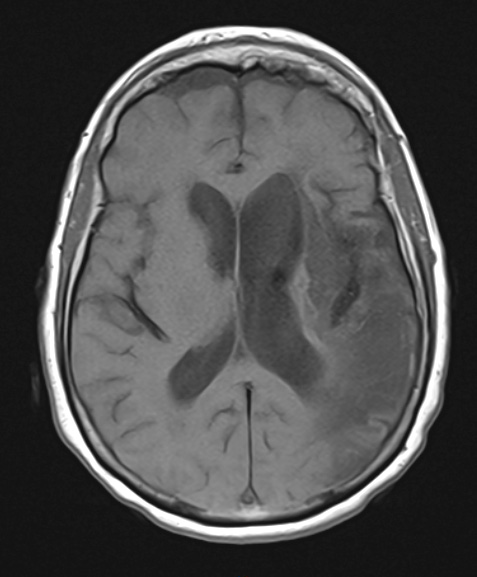

2A2,3 T1-weighted (2A2) and T2-weighted (2A3) scans showing left ventricular expansion and marked loss of parenchyma.